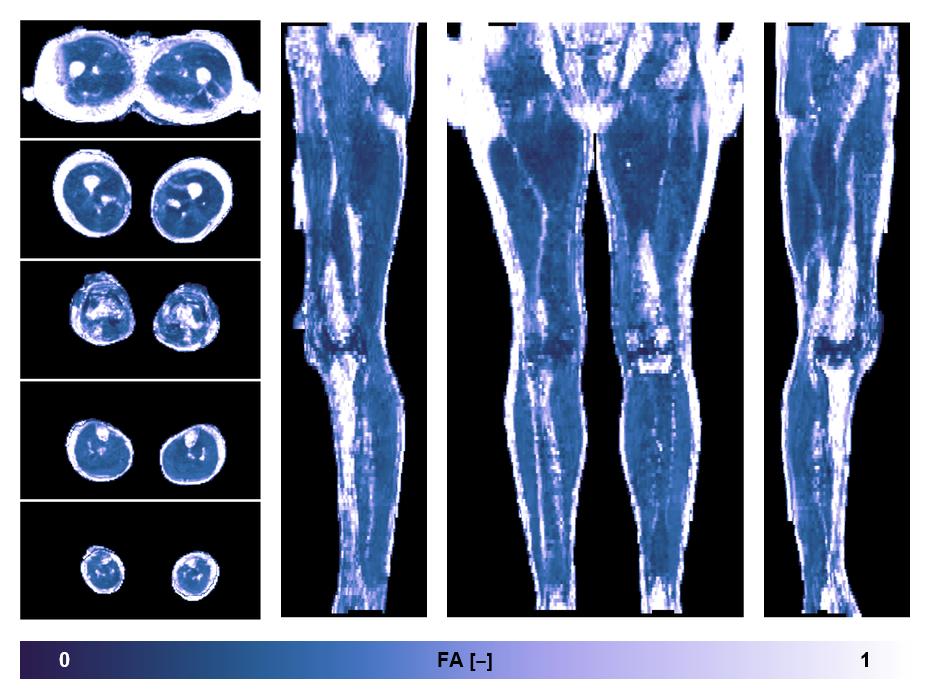

• Fractional anisotropy

IVIM corrected whole leg muscle fractional anisotropy obtained from diffusion tensor imaging.